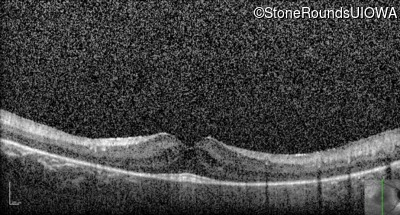

Optical Coherence Tomography - Left - 20/50

Exemplar / OCT Stack